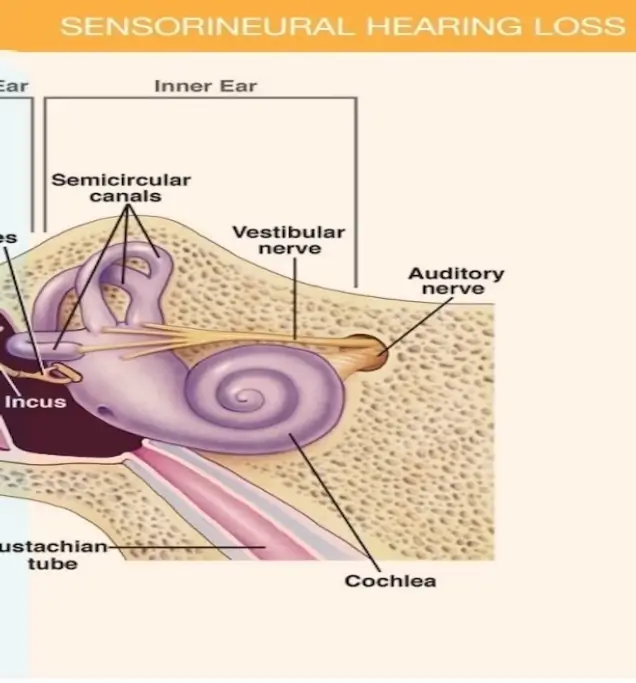

Sensorineural hearing loss happens due to damage in the inner ear (cochlea) or the auditory nerve pathways that carry sound to the brain.

It is usually permanent and the most common type of hearing loss. Causes include aging, loud noise exposure, genetics, medications, or conditions like Meniere’s disease

Advanced digital hearing aids amplify specific frequencies to enhance hearing and improve speech clarity

For individuals with severe to profound SNHL, cochlear implants bypass the damaged part of the ear, directly stimulating the auditory nerve

Devices like personal amplifiers and FM systems improve sound quality in challenging environments

Programs designed to improve listening and speech comprehension skills, particularly in noisy environments